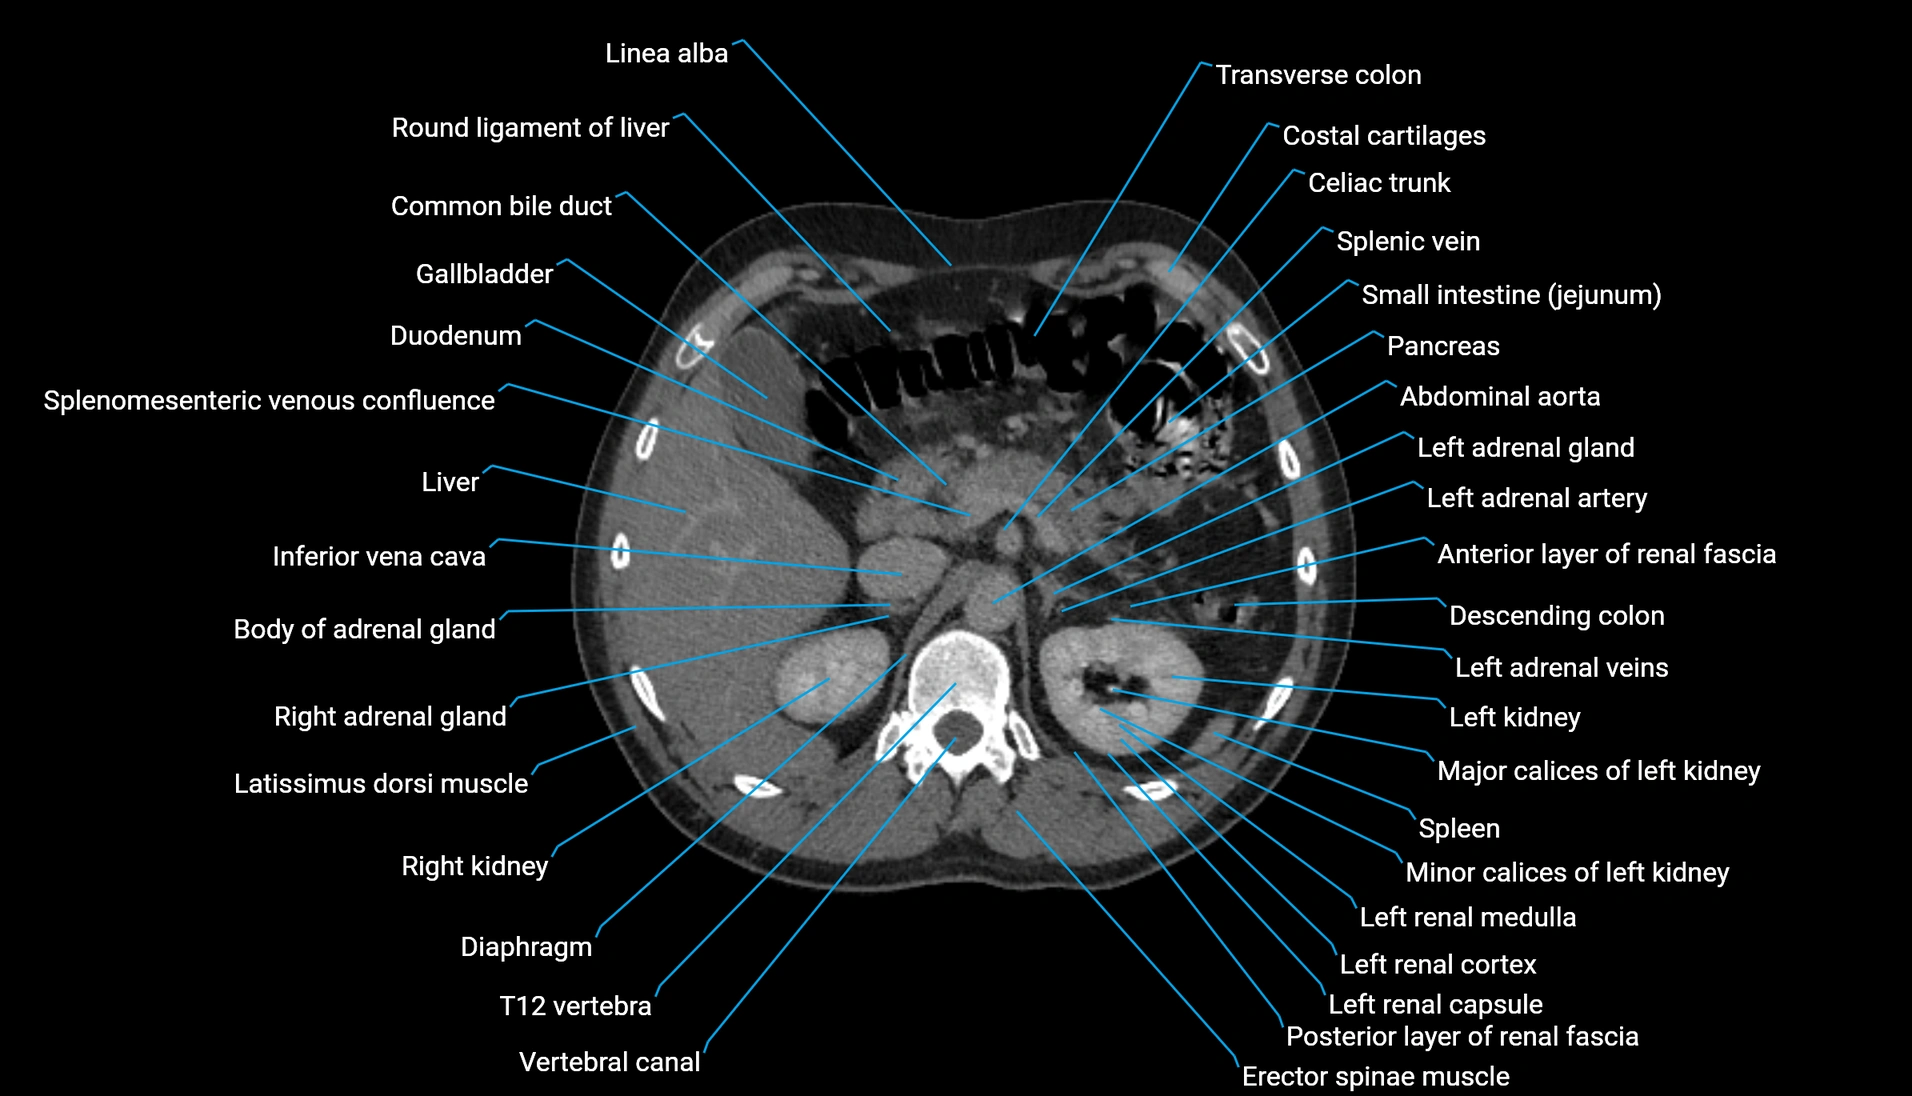

CT Appearance

Non-contrast CT:

-

Demonstrates cortical bone of acetabular rim in excellent detail

Detects fractures, dysplasia, retroversion, or bony overcoverage (pincer impingement)

3D reconstructions used in preoperative hip surgery planning

CT VRT 3D image

CT image